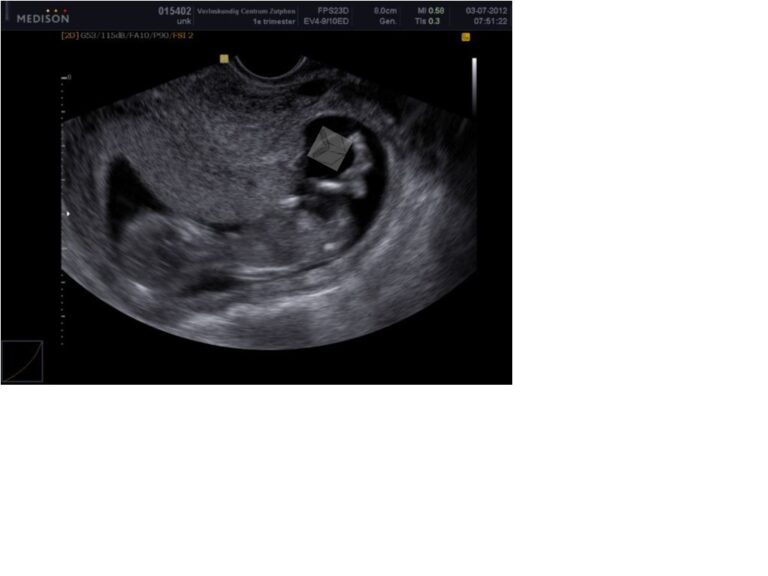

Bij onze eerste zwangerschap wilde ik dolgraag weten wat het geslacht van onze baby was. Ik zou het zo leuk vinden om een meisje te krijgen en wat een geluk, een meisje! We hebben de eerste keer alleen tegen mijn…